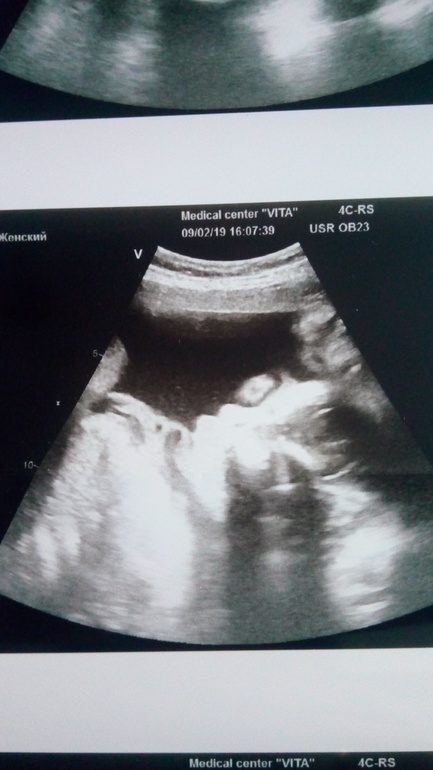

Наше УЗИ 28+4 недельки ❤

Малыш такой чудесный, навернулись слёзы! Вспомнила своих, храню и тестики и фото УЗИ. Здоровья вам, сил, лёгких родов. Не торопите время, оно быстротечно...Наслаждайтесь этим прекрасным мигом🤗

Чудесный не то слово,я не тороплю,время само летит ужасно быстро,так и не верится что во мне такой человечик живёт,уже хочется папу нашего рядом побыстрее,,он там тоже переживает ужасно за нас,но правда с мочой конешно меня напугали вчера что опасно что плохая пришла,надеюсь пересдам будет все хорошо)